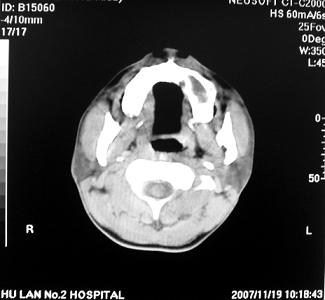

标题: CT10521:男。32岁,副鼻窦ct,请会诊。

男。32岁,鼻塞,流涕一年余。

炎性病变.息肉阻塞副鼻窦口导致窦腔内潴留.

双侧鼻腔内低密度软组织影,骨壁无明显破坏,鼻腔无扩大,双侧上颌窦、筛窦软组织影,窦壁增厚,结合临床考虑鼻息肉合并慢性上颌窦炎。